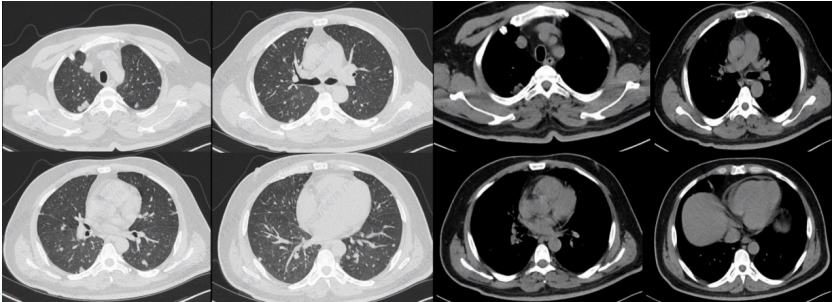

患者在严重感染打击下肺顺应性后予气管插管呼吸机辅助通气出现右侧气胸, 肺压缩约50%; 纵隔移位; 左肺炎症(图4)由于经济原因,于12月23日自动出院

图片

4  患者胸片